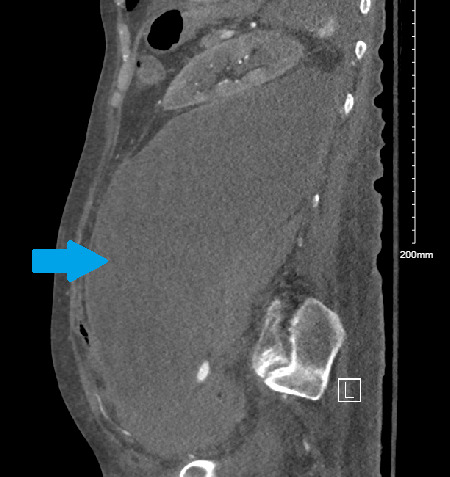

We present the case of a 70-year-old female with a history of PV on chronic steroid therapy and DVT status post inferior vena cava (IVC) filter placement on chronic anticoagulation with apixaban. She also had a chronic retroperitoneal hematoma. The patient presented with poor appetite and somnolence. In the emergency department, she was hypotensive with blood pressure of 70/50 mmHg and tachycardic with a heart rate of 110 bpm, reporting diffuse abdominal discomfort. She was afebrile, with clear lung sounds, and no abdominal tenderness on exam. Initial workup was significant for a lactate level of 3.6 mmol/l, which trended upwards to 4.2 mmol/L before fluids were administered, and a low white blood counts of 3.08 x10(9) /L (table 1). Her imaging revealed an increase in the size of her left retroperitoneal hematoma and perivascular inflammatory changes, raising concerns for a superimposed infection (figure 1). Sepsis treatment was initiated after which the patient was hemodynamically stable. However, a new left-sided hydronephrosis and concern for ureteral extravasation on imaging raised suspicion for urinoma as a source of sepsis. The hematoma size measured 26.4 x 12 x 10 cm on imaging. Radiologic evaluation demonstrated a 1.4 cm focus of contrast blush consistent with active urine extravasation but the urinoma was challenging to measure as imaging primarily visualized the contrast blush.

_showing_left_retro-peritoneal_fluid_collection_(blue_arr.png)